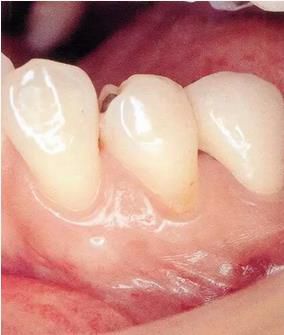

▲圖1

牙位異常例①。由于牙列擁擠造成牙根接近。